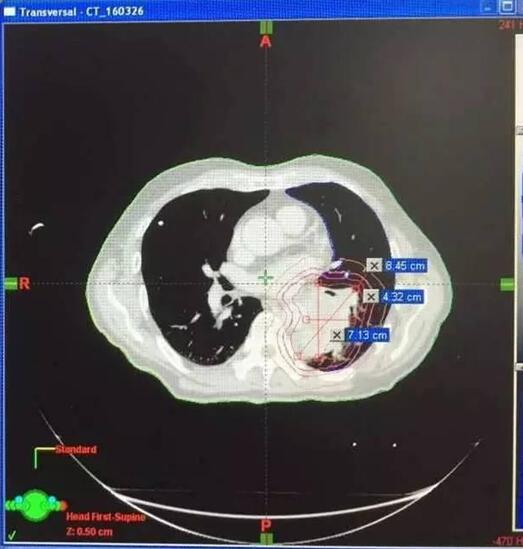

患者男性,64岁。

2016年3月,诊断为小细胞肺癌。

治疗前

治疗后病灶明显缩小